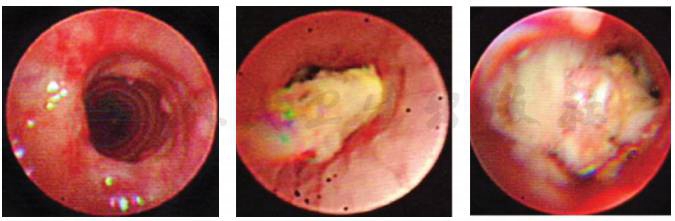

转入笔者科室立即完善相关病原学检查提示GM试验阴性,1,3-β-D葡聚糖 <10µg/L,痰培养及血培养均阴性,PPD 阴性,结核斑点试验(T-spot)阴性,以上检查均未找到明确病原体。入院第5天完善纤维支气管镜检查,镜下示(图3)右肺下叶B10亚段可见大量黄白色类干酪样物质阻塞及坏死黏膜附着管壁,予毛刷刷检,刷检时黏膜有出血,予万分之一盐酸肾上腺素冲洗止血,将刷检物质送病理检查。根据镜下改变,高度怀疑支气管内膜结核及真菌感染。经胸科医院会诊,建议诊断性抗结核治疗,但家属拒绝。给予患儿伏立康唑抗真菌治疗,7天后体温恢复平稳,无咯血,复查肺CT(图4)提示右肺下叶后底段支气管旁高密度团块影较前减小。入院第12天病理结果回报(图5)提示炎性渗出坏死物及霉菌。

图4 支气管镜后7天复查肺CT